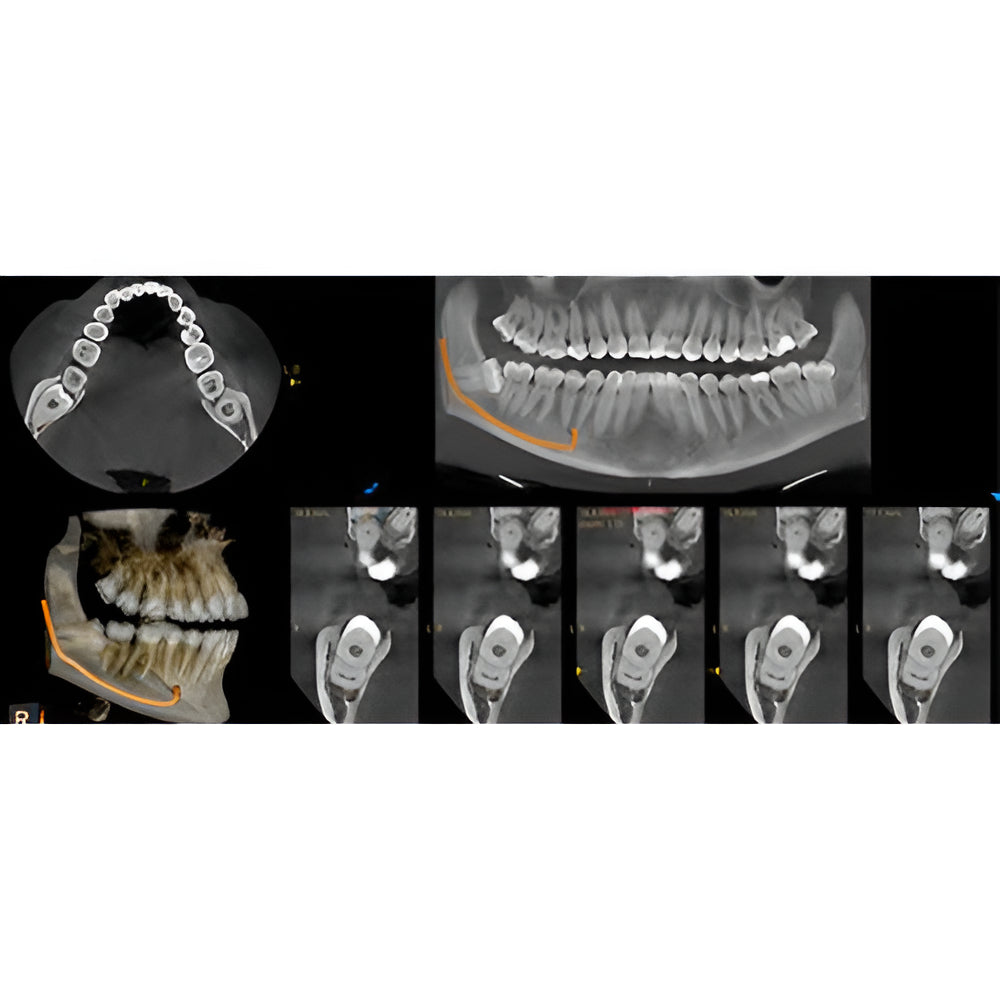

Enter a world of crystal-clear 3D images with the CS 8200 3D Access-a CBCT system that’s state-of-the-art, but intuitive and easy to use, taking your dental practice to the next level. Enjoy CBCT imaging that’s easier than you think and built on an open platform so that you can activate your future practice here and now.

- Field Of View: 4x4, 5x5, 8x5, 8x9, 12x5, 12x10

- Versatile 4-in-1 solution ideal to expand treatment options

- Easy to use with a modern, user-friendly interface